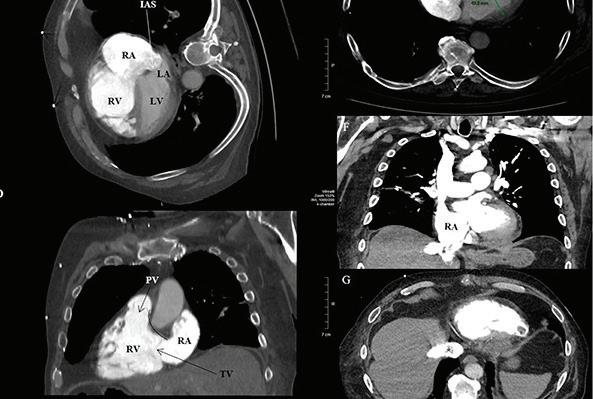

CT (COMPUTERIZED TOMOGRAPHY) SCANNER

How will it make care better? We need to replace our heavily used CT scanner to improve patient care and wait times.

Costs: 4.9 Million

“Our commitment to cutting-edge research in unwavering and an extra CT scanner would bolster our research capabilities and contribute to advancements in cardiac imaging technologies. This investment will elevate the UOHI’s ability to provide high-quality cardiac imaging services and positively impact patient care.”

- Gerri-Anne Kay, Director, Cardiac Imaging